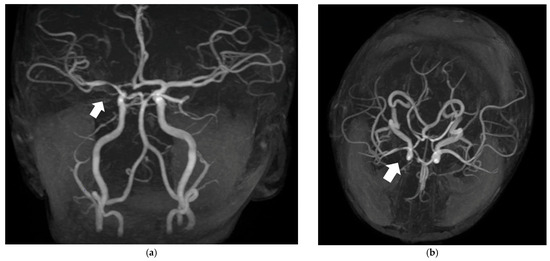

Post-Varicella Arteriopathy as a Cause of Pediatric Arterial Ischemic Stroke: A Systematic Review and Case Report

Background/Objectives: Post-varicella arteriopathy (PVA) is a significant cause of pediatric arterial ischemic stroke (AIS) that typically involves previously healthy children within 12 months of primary varicella infection, mostly with a monophasic course. Diagnosis is based on clinical and imaging findings, and cerebrospinal fluid analysis may confirm it; treatment is empirical and heterogeneous. We describe a typical case of PVA and present a systematic review of its clinical, radiological, therapeutic, and outcome features. Methods: Following PRISMA 2020 and AMSTAR-2 guidelines, data on demographics, clinical presentation, imaging, laboratory confirmation, treatment, and outcomes were extracted across databases (PubMed, Embase, Scopus). Results: Forty-seven studies, encompassing 312 pediatric patients, were included. Mean age was 4 years with a median latency of 3.82 months from varicella to neurologic symptoms. Common presentation included hemiparesis, language impairment, and seizures. Imaging findings showed unilateral focal involvement of anterior circulation arteries, basal ganglia infarctions, and, rarely, bilateral or posterior circulation involvement. CSF VZV-DNA PCR and anti-VZV IgG were positive in 39% and 48% of tested patients. Treatment included intravenous acyclovir (34%), corticosteroids (20%), and low-dose aspirin (77%); two patients underwent acute reperfusion therapy (rt-PA or thrombectomy). Outcomes tended to be moderately favorable: 43% achieved full recovery, 45% had residual deficit, and 11% experienced recurrence. Prothrombotic state was reported, and it may influence disease severity. Conclusions: PVA is a rare distinct cause of pediatric stroke, with a generally favorable prognosis quoad vitam. Standardized guidelines and prospective studies are needed to establish evidence-based management. Clinicians should maintain a high suspicion for its diagnosis. Full article

Show Figures

Figure 1